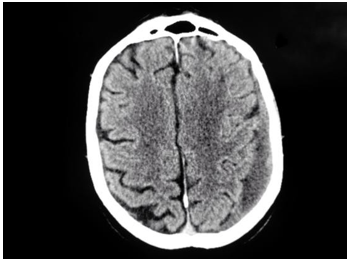

Concomitant Pontine and Cerebellar Infarction Due to Traumatic Vertebral Artery Dissection Secondary to a Cervical C2 Fracture